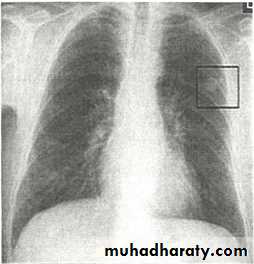

Nodular (coin) lesion in the left upper lung with irregular edge (most probably cancinoma